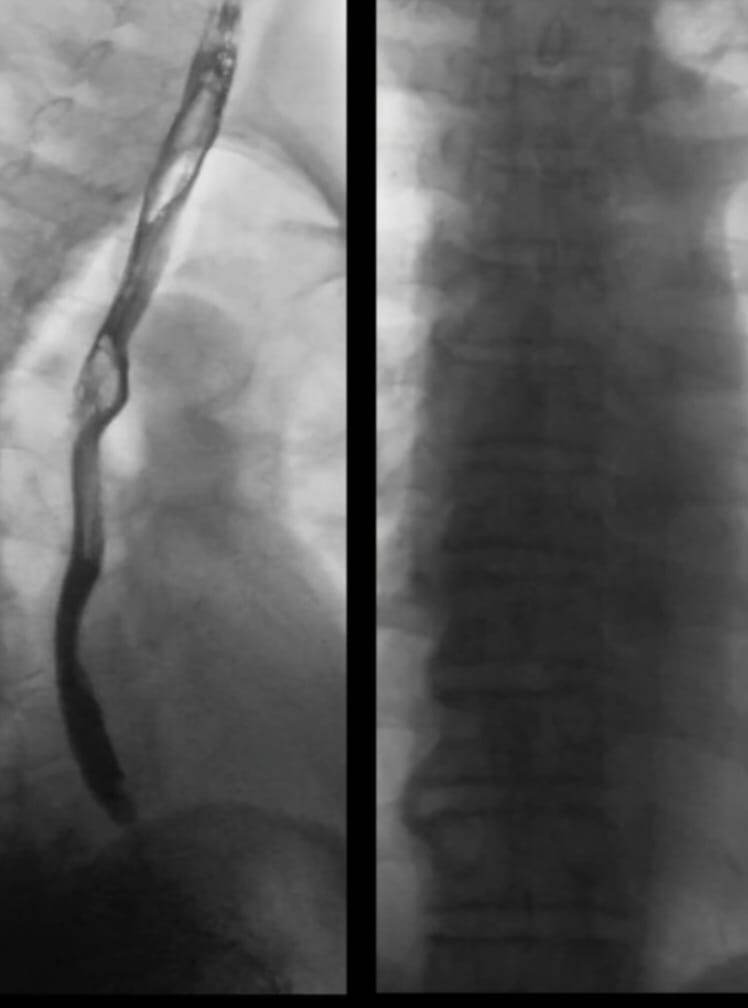

При глотании запускается процесс перистальтики пищевода — непроизвольные волнообразные сокращения и расслабления мышц, которые проталкивают пищу или жидкость в желудок. Современные методы наблюдения, такие как высокоразрешающая манометрия, показывают, что этот процесс чрезвычайно сложен.

«Например, нижний пищеводный сфинктер, который действует как клапан между пищеводом и желудком, открывается только в нужный момент, чтобы пропустить пищу. Кроме того, при быстрых повторных глотаниях они подавляют друг друга, и проходит только последнее сокращение — это явление известно как деглутитивное торможение. Однако до сих пор у нас не было модели, которая могла бы воссоздать все эти сложные движения или нарушения моторики», — поясняет ведущий автор исследования, профессор Такаси Миура из Медицинского факультета Университета Кюсю.

Новая модель использует простые математические уравнения в сочетании с данными манометрии для имитации всего процесса моторики пищевода. Она учитывает сигналы, возникающие в мозге и в локальных нервных сплетениях пищевода, а также сокращение и расслабление его мышц и нижнего сфинктера.